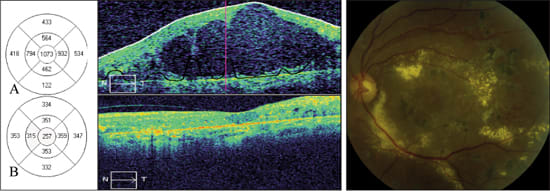

An 82-year-old female with insulin dependent diabetes mellitus was evaluated for proliferative diabetic retinopathy (PDR) and diabetic macular edema in both eyes. Her other medical problems reported in the history included hypertension and chronic obstructive pulmonary disease. Her ophthalmic history included a combined pars plana vitrectomy with cataract surgery two years earlier. Best corrected visual acuity in the right eye was 20/400 and SD-OCT showed CME with a central foveal thickness of 841 microns (Figure 3A).

Figure 3. Sequential SD-OCT images from an 82-year-old female with diabetic macular edema in the right eye. Color fundus photograph shows exudates with macular thickening.

A: Horizontal scans through the fovea show distortion of the normal foveal contour with a large central intraretinal cyst. The retinal map shows a central foveal thickness of 841 μm. Best-corrected visual acuity was 20/400.

B: One month after intravitreal triamcinolone acetonide, SD-OCT reveals marked improvement of foveal thickness (113 μm) and resolution of cystoid macular edema. Best-corrected visual acuity remained 20/400.

The right eye was treated with intravitreal triamcinolone acetonide (40 mg/ml). One month later, her vision remained 20/400 although the patient noted subjective improvement. SD-OCT measured central foveal thickness improved to 113 microns and there was restoration of the foveal contour (Figure 3B).

A 43-year-old man with a 19-year history of non-insulin dependent diabetes mellitus was referred for diabetic macular edema. He had multiple prior panretinal photocoagulation and focal laser treatments. Best corrected visual acuity was 20/400 in the left eye and SD-OCT showed a central foveal thickness of 1073 microns (Figure 4A).

Figure 4. Sequential SD-OCT images from a 43-year-old male with diabetic macular edema in the left eye. Color fundus photograph demonstrates diffuse exudates with macular edema.

A: Horizontal scans through the fovea show distortion of the normal foveal contour with a very large intraretinal cyst. The retinal map shows a central foveal thickness of I073 μm. Best-corrected visual acuity was 20/400.

B: Six weeks after intravitreal triamcinolone acetate, SD-OCT reveals marked improvement of foveal thickness (262 μm) and restoration of the foveal contour. Best-corrected visual acuity remained 20/400.

The left eye was treated with intravitreal triamcinolone acetate (4mg/0.1ml). At six weeks, the patient's best corrected visual acuity remained 20/400 but central foveal thickness improved to 257 microns (Figure 4B). The patient was subsequently treated with focal laser photocoagulation.